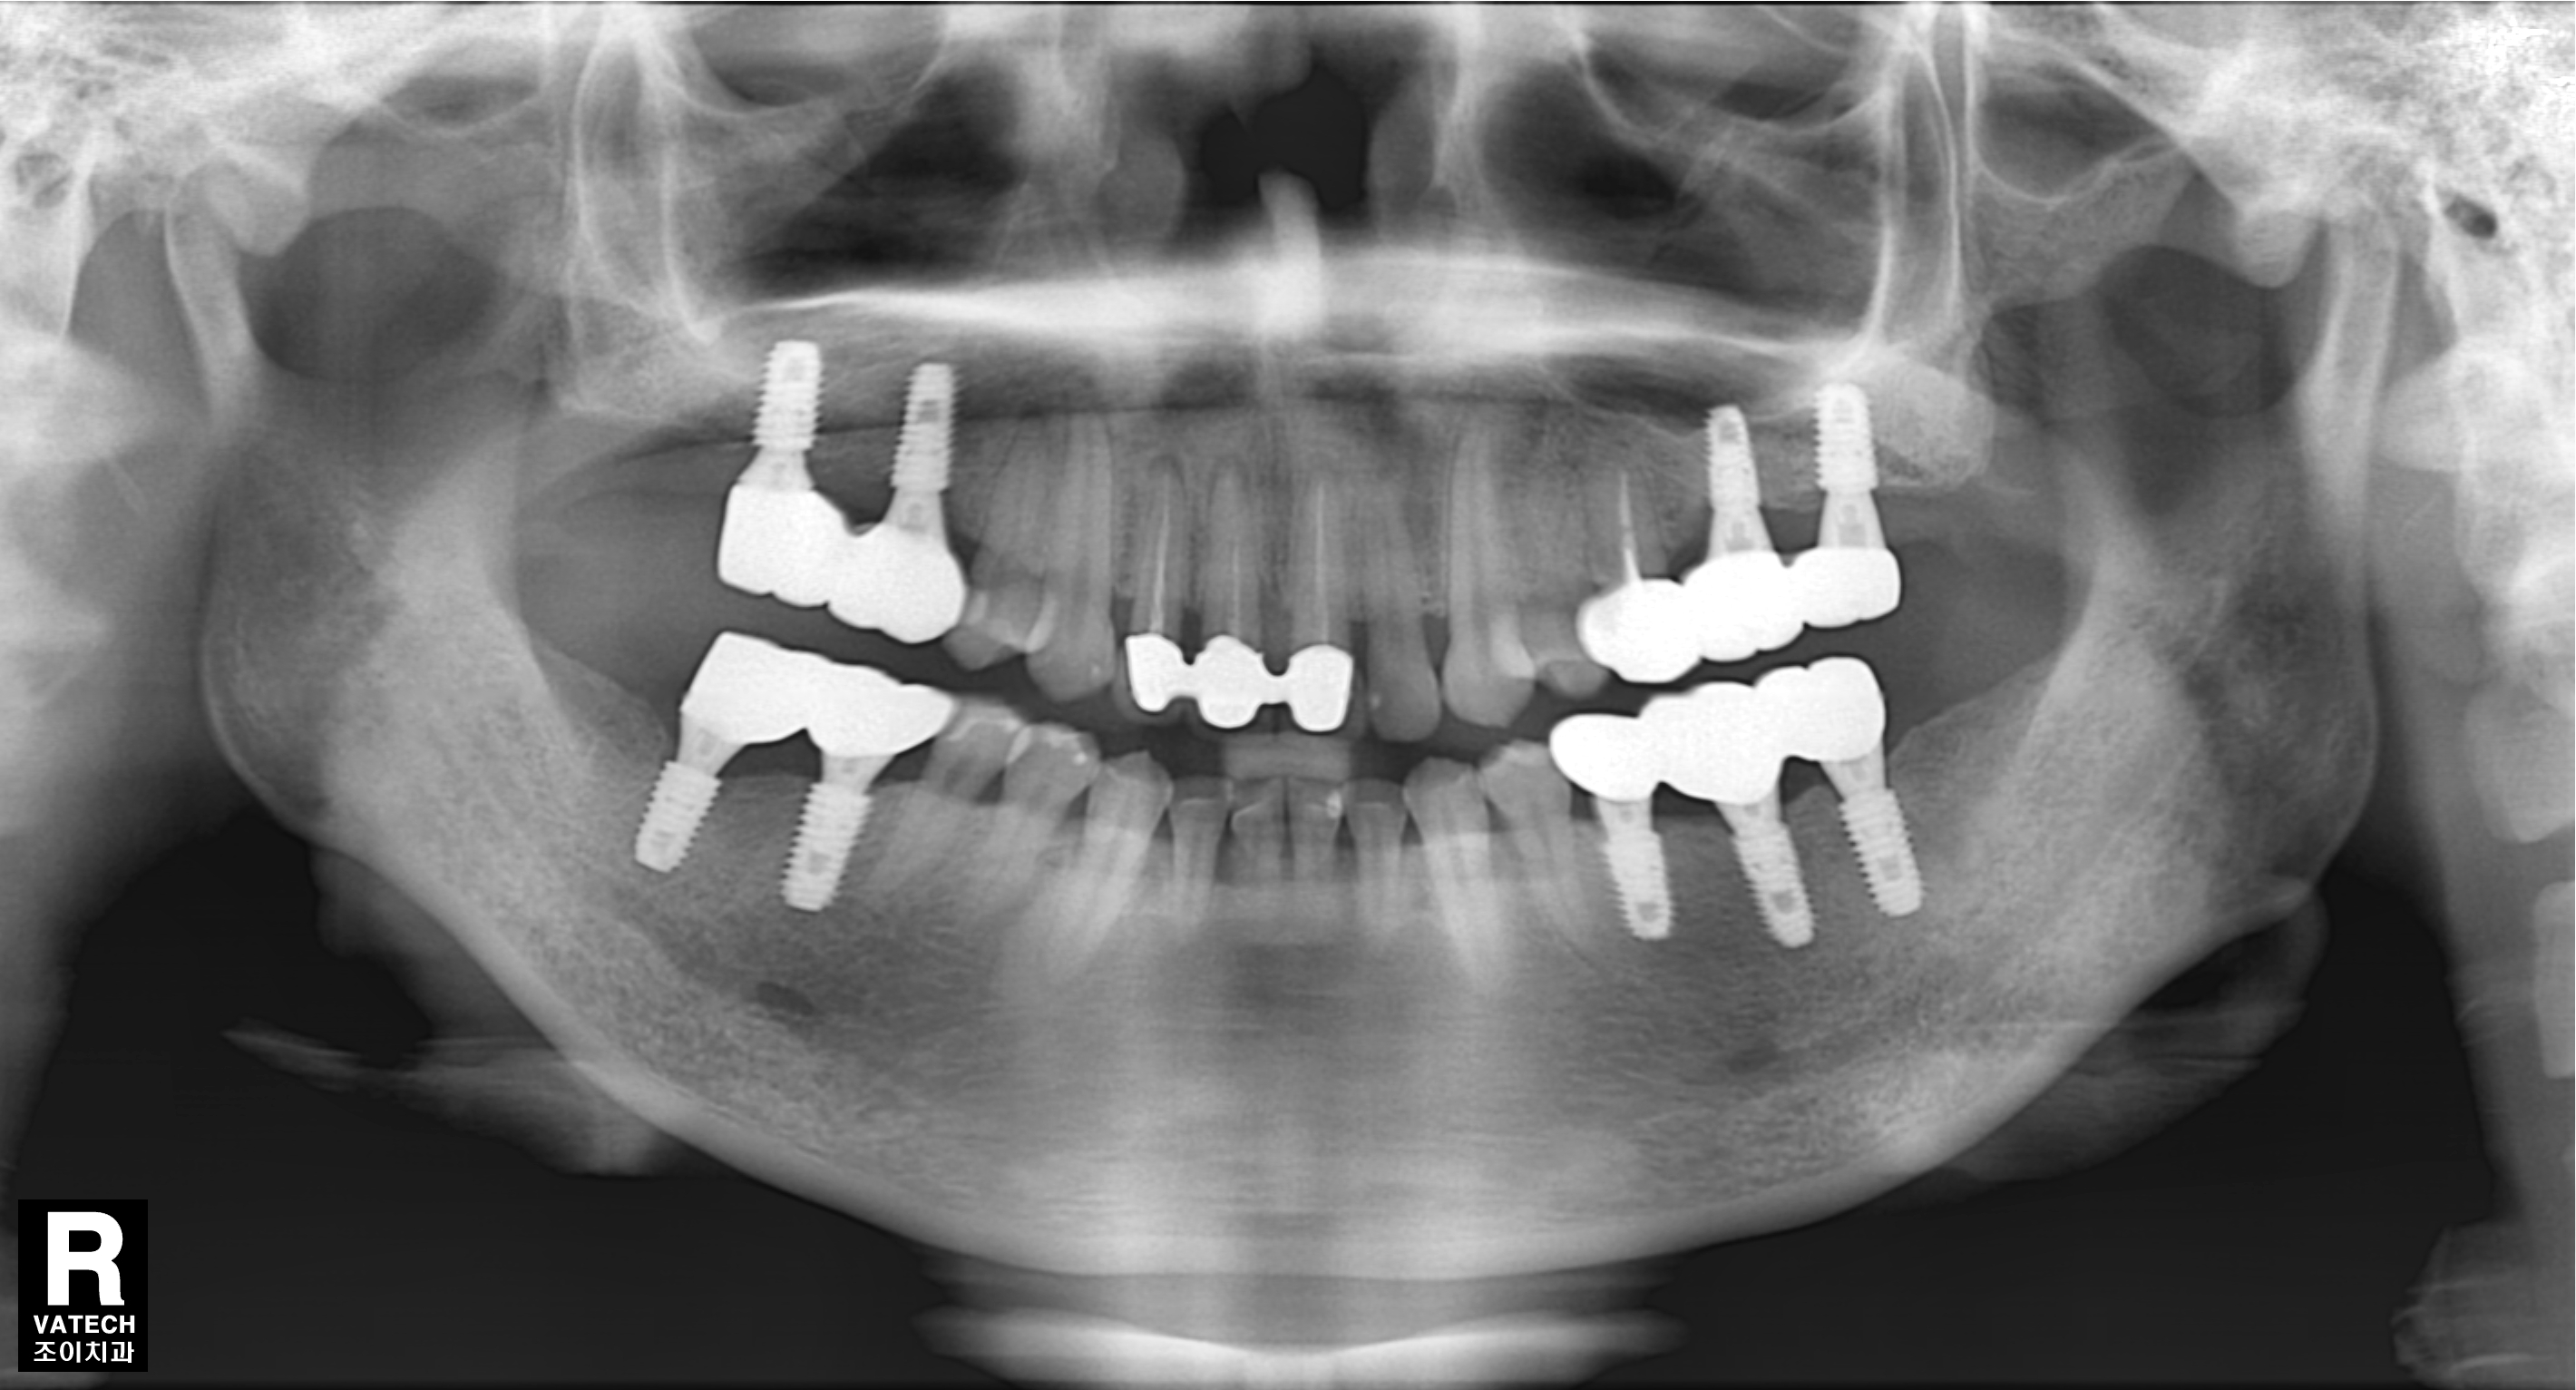

[임플란트] 제목 : 충치 및 치주질환 임플란트

충치와 치주질환에 의한 치아상실로 임플란트 치료함.